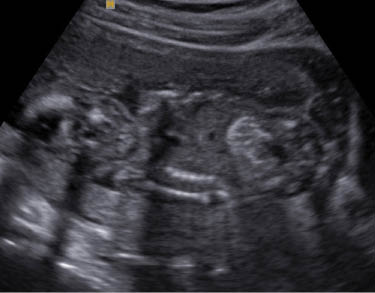

Club foot

Club foot (talipes equinovarus) is an abnormal relationship of the foot/ankle to the tibia and fibula. The foot is excessively planter flexed with the forefoot bent medially and the sole facing inward. It occurs in 0.1–0.4% of pregnancies and is bilateral 60% of the time. It is also more common in males.

The best way to detect it with US is when the long axis of foot is in same plane as the long axis of the tibia and fibula [33]. Club foot may occur in isolation or in association with numerous other conditions, such as general musculoskeletal disorders, arthrogryposis, genetic syndromes, neural tube defects and spine defects [33]. In 10–14% of cases it coexists with other structural malformations. First degree relatives of a person with idiopathic club foot are at a higher risk of having a club foot when compared with the general population [34]. The risk of a subsequent pregnancy being affected by club foot is 2% if a previous male fetus was affected and 5% if the previous affected fetus was female [34].

In 6–22% of cases it is associated with aneuploidy, with trisomy 18 being the most common [35]. Most cases of club foot with concominant chromosomal anomalies will demonstrate other structural abnormalities. Therefore chromosomal analysis is recommended upon evidence of additional structural anomalies. In the absence of other structural anomalies, oligohydramnios, and IUGR isolated club foot has not been associated with adverse pregnancy outcomes. Post natal successful surgery is obtained in 52–91% of cases enabling most children to participate in normal activities [34].